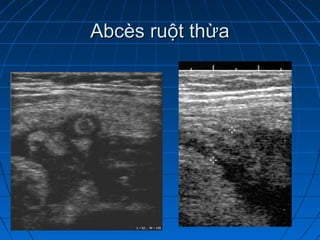

Abcès ruột thừaAbcès ruột thừa